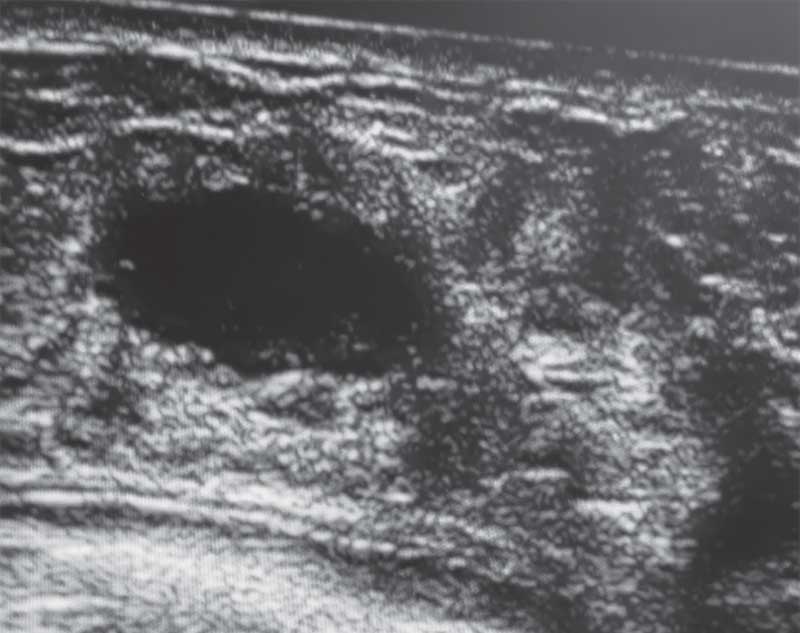

Рис. 13. Эхограмма галактоцеле правой молочной железы у пятилетней девочки

Галактоцеле

Киста, заполненная молокоподобным содержимым, формируется при аномалиях протоковой системы, клинически проявляется увеличением железы. При УЗИ наблюдается пониженная эхогенность, иногда перегородки, единичные локусы кровотока по ЦДК, возможен горизонтальный уровень жидкости [5, 7, 10]. Эхограмма галактоцеле правой МЖ у девочки в возрасте пяти лет представлена на рис. 13.